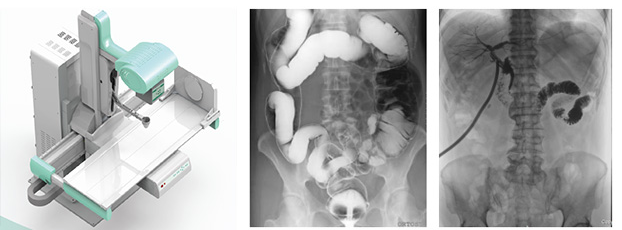

近年來(lái),DR設(shè)備正朝著更加準(zhǔn)確化、輕便化、智能化和多維化方向發(fā)展,出現(xiàn)了多功能動(dòng)態(tài)DR、移動(dòng)DR、三維化DR產(chǎn)品等等。其中多功能動(dòng)態(tài)DR大大提高了普通放射設(shè)備準(zhǔn)確診斷的能力,為臨床創(chuàng)造了價(jià)值。接下來(lái)給大家分析下多功能動(dòng)態(tài)DR是如何提高工作效率的。以下是部分體位介紹及解決方案:

應(yīng)用多功能動(dòng)態(tài)DR后,在攝片中很好地解決了上述問(wèn)題。因?yàn)樵诓僮鞫喙δ軇?dòng)態(tài)DR檢查時(shí),患者可取平臥位,作張口狀,球管中心線從兩口角連線的中點(diǎn)垂直射入,可先使用多功能動(dòng)態(tài)DR的低劑量透視功能,讓病人調(diào)整好的攝片角度后進(jìn)行曝光,一次即可成功。從而降低了醫(yī)生擺位要求,減少重復(fù)曝光現(xiàn)象。

在這些對(duì)球管中心線和受檢部位形成角度有要求的體位的擺位過(guò)程中,可以應(yīng)用多功能動(dòng)態(tài)DR的電動(dòng)控制擺臂、數(shù)字顯示角度值和動(dòng)態(tài)透視影像觀察功能等特性,使這些體位的擺位更加準(zhǔn)確、讓醫(yī)生工作效率更高!如果您想采購(gòu)普愛(ài)醫(yī)療的多功能動(dòng)態(tài)DR,或了解產(chǎn)品技術(shù)參數(shù),歡迎聯(lián)系我們。